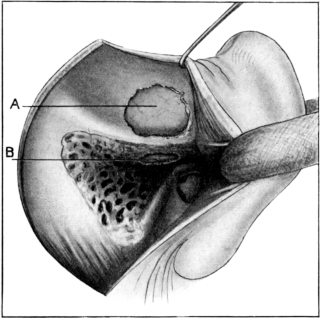

| 336. | Killian’s Operation upon the Frontal Sinus | 644 |

| 337. | Killian’s Operation upon the Frontal Sinus | 644 |

| 342. | Killian’s Operation upon the Frontal Sinus | 646 |